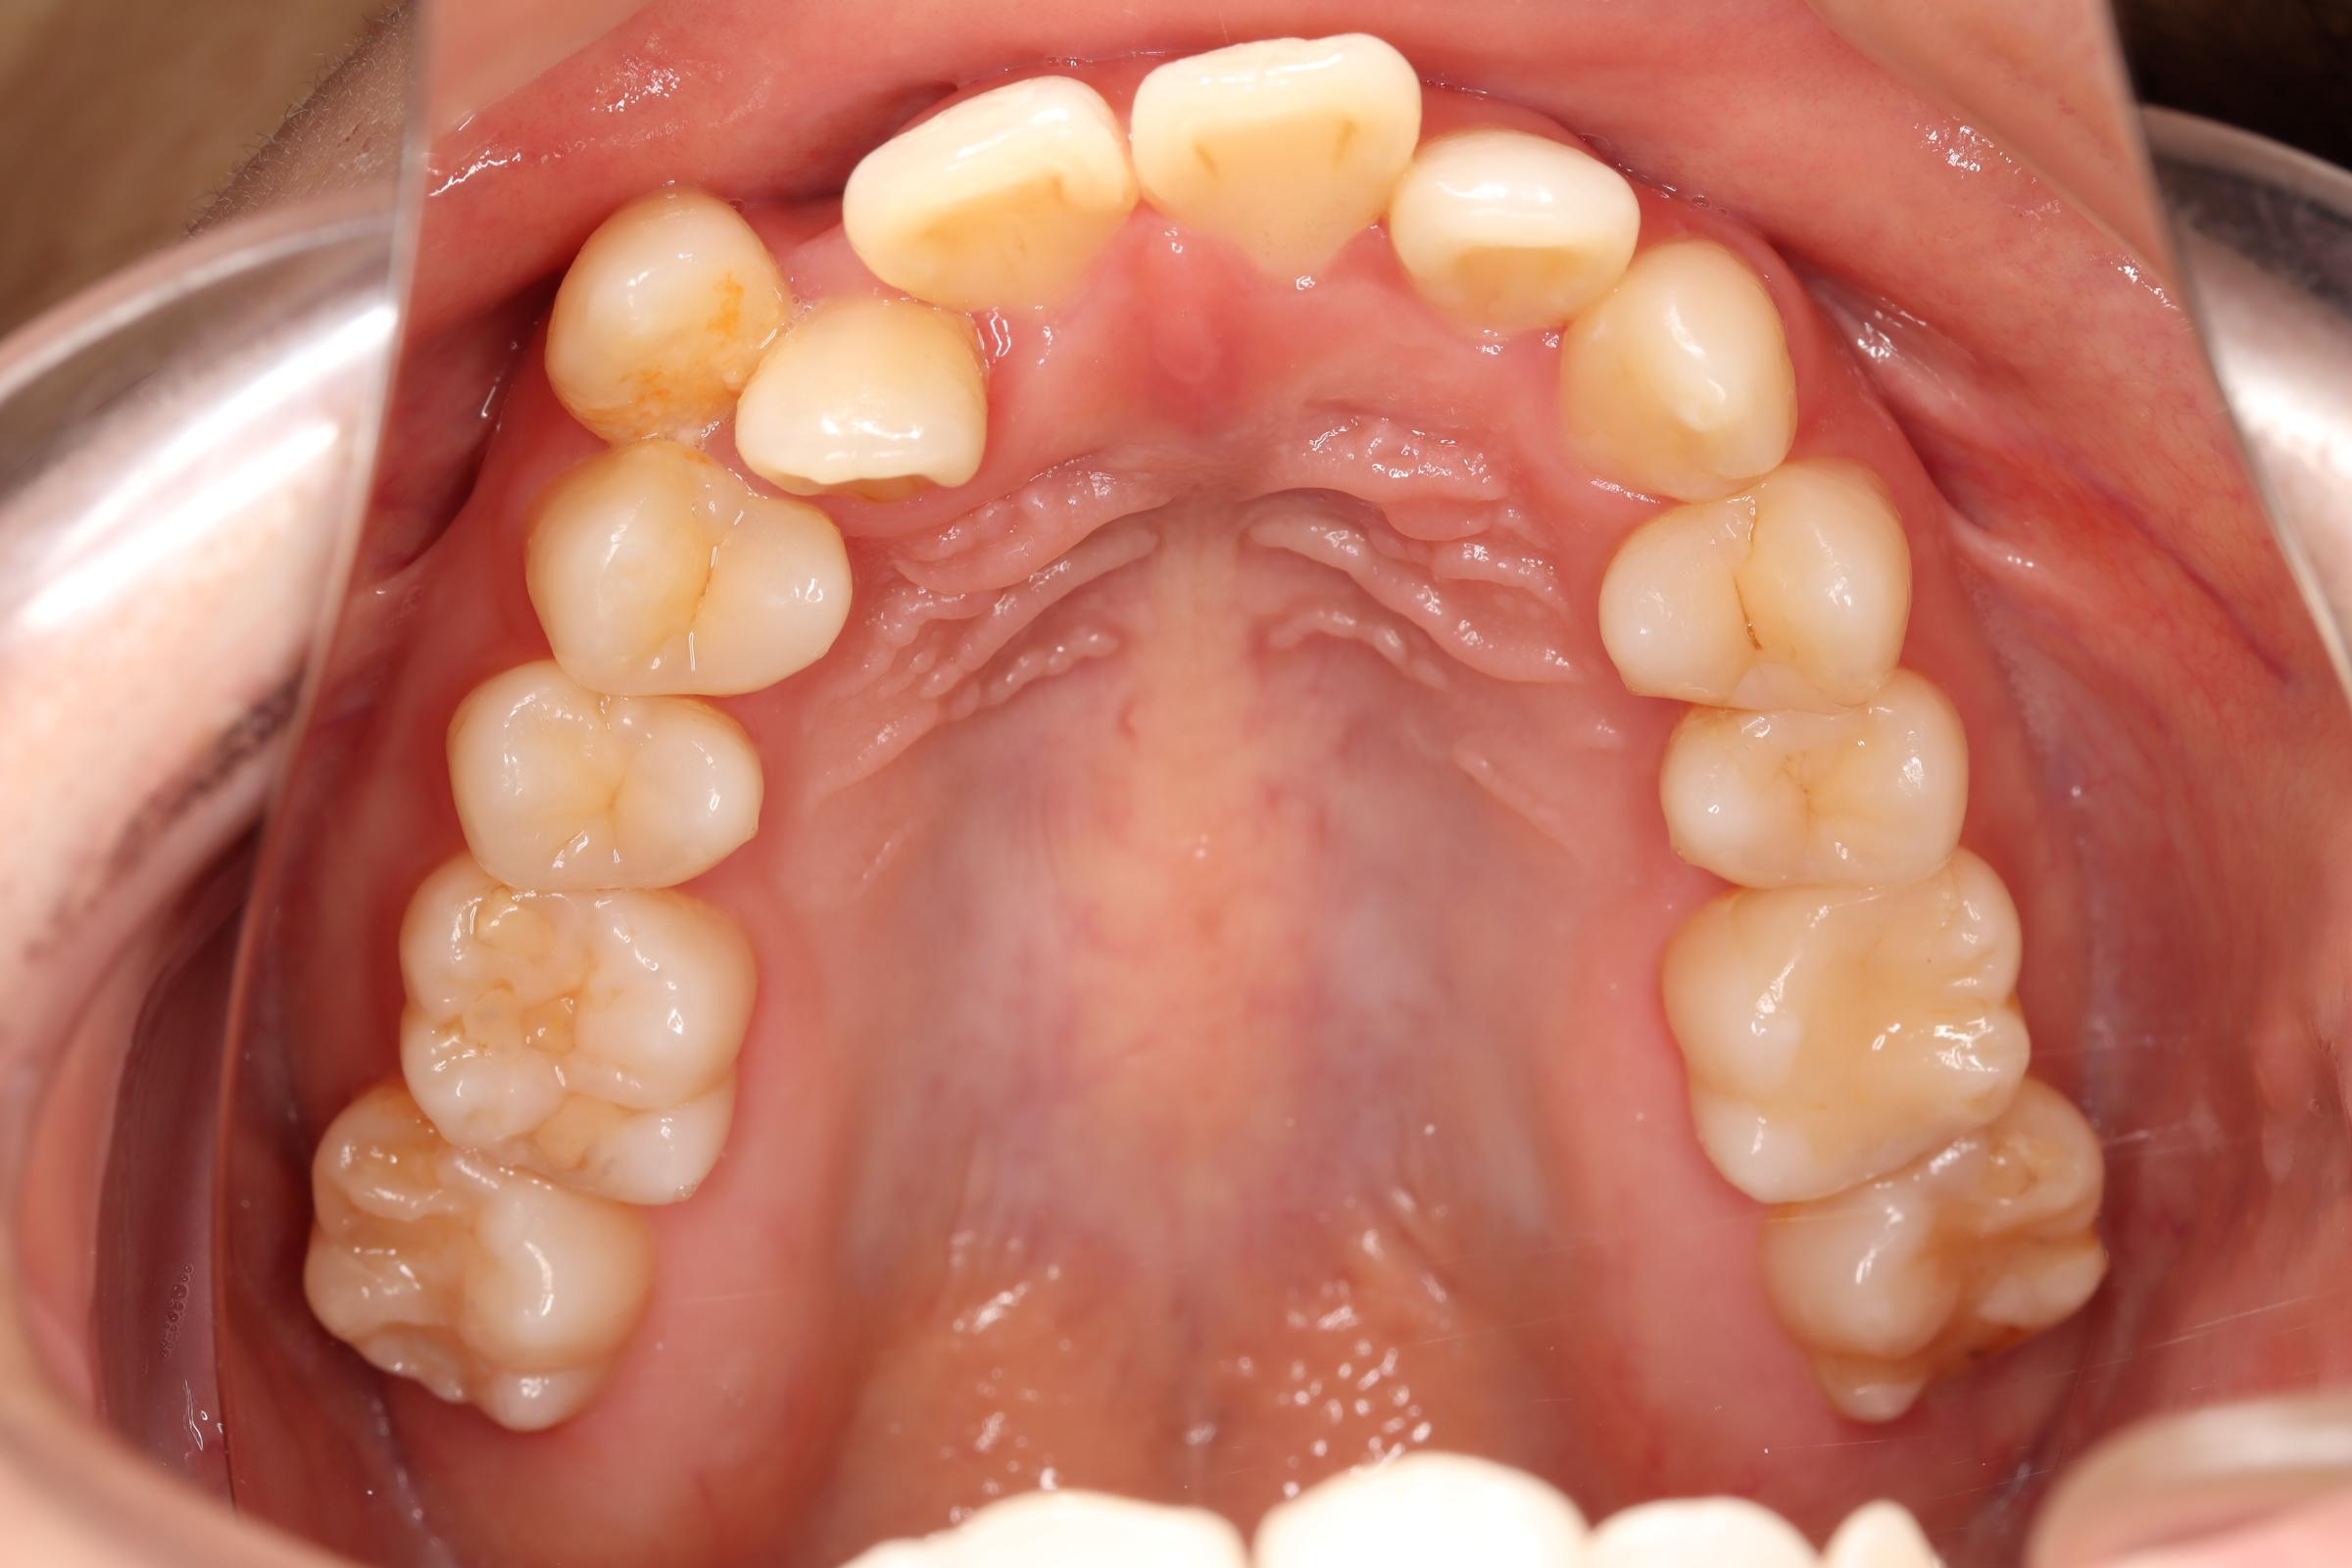

舌側(リンガル)矯正での叢生(ガチャ歯)の治療

口腔内の変化

| 治療前 | SNSなどで「ガチャ歯」と呼ばれている、見た目のがたつきを治したかった患者さんです。 骨格的な問題はありませんでしたが、上下の前歯が唇側傾斜しており、上下顎前突症で口元の突出感がありました。 |